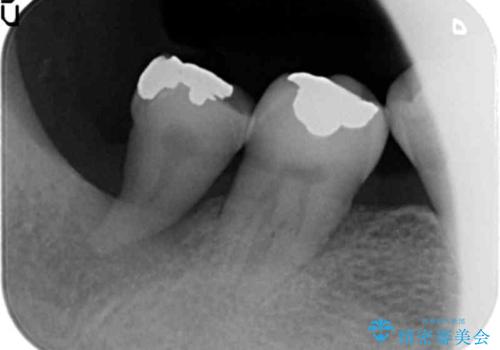

- 右下の親知らずが咬むと痛いとのことでした。

親知らずを抜いて、倒れこんでいる手前の歯を矯正治療で移動させ、ブリッジにしました。

矯正治療をしなければ、倒れこんでいる影響で手前の奥歯も含めて歯周病で悪化してしまうため、しっかり起こして治療をしました。